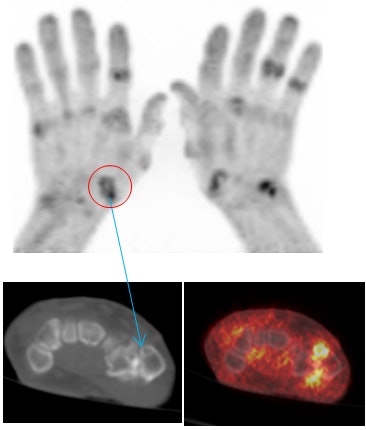

![]() |

| Areas of uptake in the metacarpal joints show similarly on PEM (above) and PET/CT (below). There is evidence of joint space narrowing likely due to FDG uptake in areas of corrosive inflammatory osteoarthritis. All images courtesy of Dr. Joyce Mhlanga. |